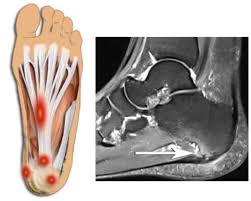

이 질환은 발밑의 족저근막에 염증이 생겨 발뒤꿈치에서 발가락까지 이어지는 섬유띠가 영향을 받는 질환으로, 중장년층 뿐만 아니라 젊은 세대에게도 흔하게 발생합니다.

족저근막염은 다양한 원인이 있습니다. 발의 구조적인 이상인 평발이나 요족 등이 원인일 수 있지만, 대부분은 발을 과도하게 사용하여 발생합니다.

✅족저근막염 주요 증상

족저근막염은 발바닥의 근막에 염증이 생기는 흔한 발목 문제 중 하나입니다. 이 질환은 다양한 증상을 동반하며 환자들에게 불편함을 초래합니다. 주요 족저근막염의 증상은 다음과 같습니다: